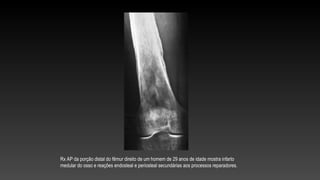

Rx AP da porção distal do fêmur direito de um homem de 29 anos de idade mostra infarto

medular do osso e reações endosteal e periosteal secundárias aos processos reparadores.